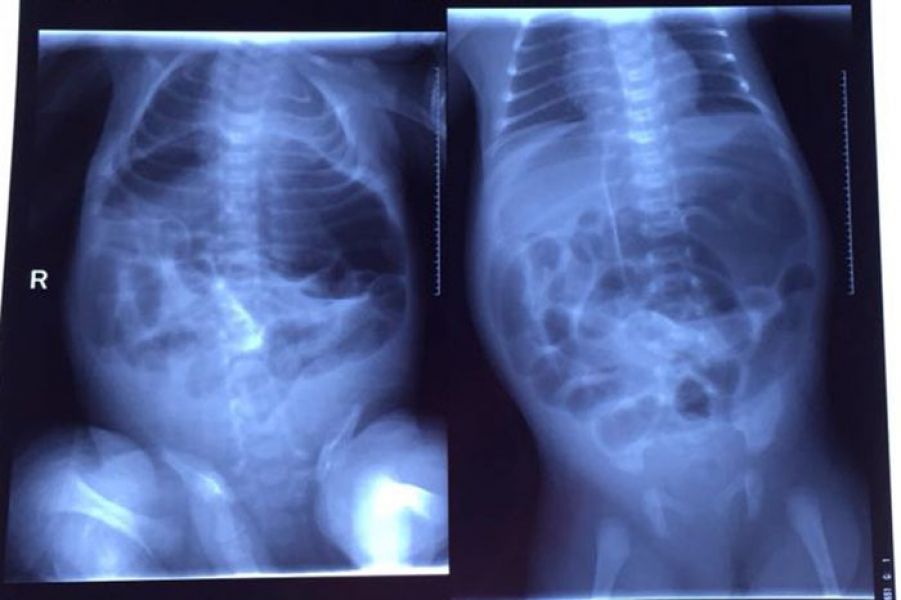

产后42小时,小女因身体孱弱即入住新生儿重症监护室,出生时体重仅仅2.2公斤。初步诊断为“早产儿;低体重儿;新生儿败血症”,当天腹部检查未见异常。第二天,患儿进食少许奶水后出现腹胀,呕吐。急诊行B超检查提示“腹腔积液,肠管扩张”;腹部X线片检查提示“腹部大小肠管扩张积气,双侧膈下游离气体考虑气腹”。急诊请普外五科会诊。

手术前X线检查图片